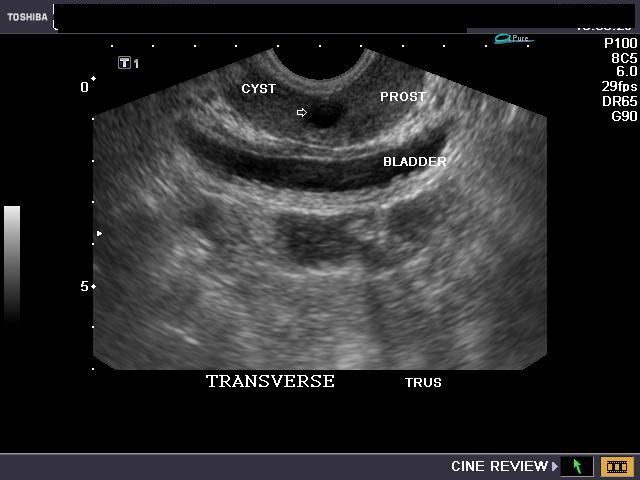

Large cyst of seminal vesicle

This elderly male patient had history of dysuria and urgency and other symptoms of prostatism. TRUS sonography (Transrectal ultrasound) showed a large cyst just above and to the left of the prostate. The cyst measured 3.6 x 2.8 cms. and showed clear fluid contents. Color and Power Doppler showed no significant findings. The cyst contained no septae or solid nodules and was non calcific. These findings suggest a large cyst of the left seminal vesicle. Both kidneys appeared normal. (BL= BLADDER; PROS= PROSTATE). The TRUS image of prostate (transverse)- in topmost row shows evidence of co-existing early benign prostatic hypertrophy. The main differential diagnoses in this case include: ejaculatory duct cysts; these are usually in the midline and have a tapering appearance; the others include prostatic utricle cysts which are present within the midline of the prostate. Seminal vesicle cysts may be congenital or acquired.